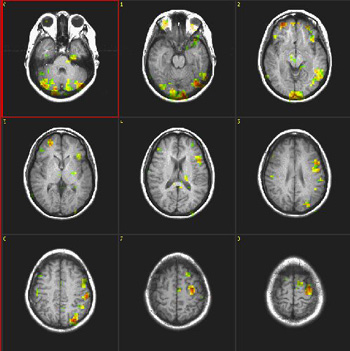

Phonological Fluency

| Subject |

Right handed, 37 year-old woman |

| Paradigm |

ON: Retrieving words starting with a given letter

OFF: Think of a dark sky |

| Statistics |

| Statistical method |

P Value |

Z score |

| Correlation coeficient |

0.0001 |

N/A |

|

| Images |

| Activation |

This paradigm elicits activation of the superior aspect of Broca's and Brodman's 37 areas. Some activation appears in parasagital parietal areas. The color in the left pterional fossa is due to vascular inflow. |